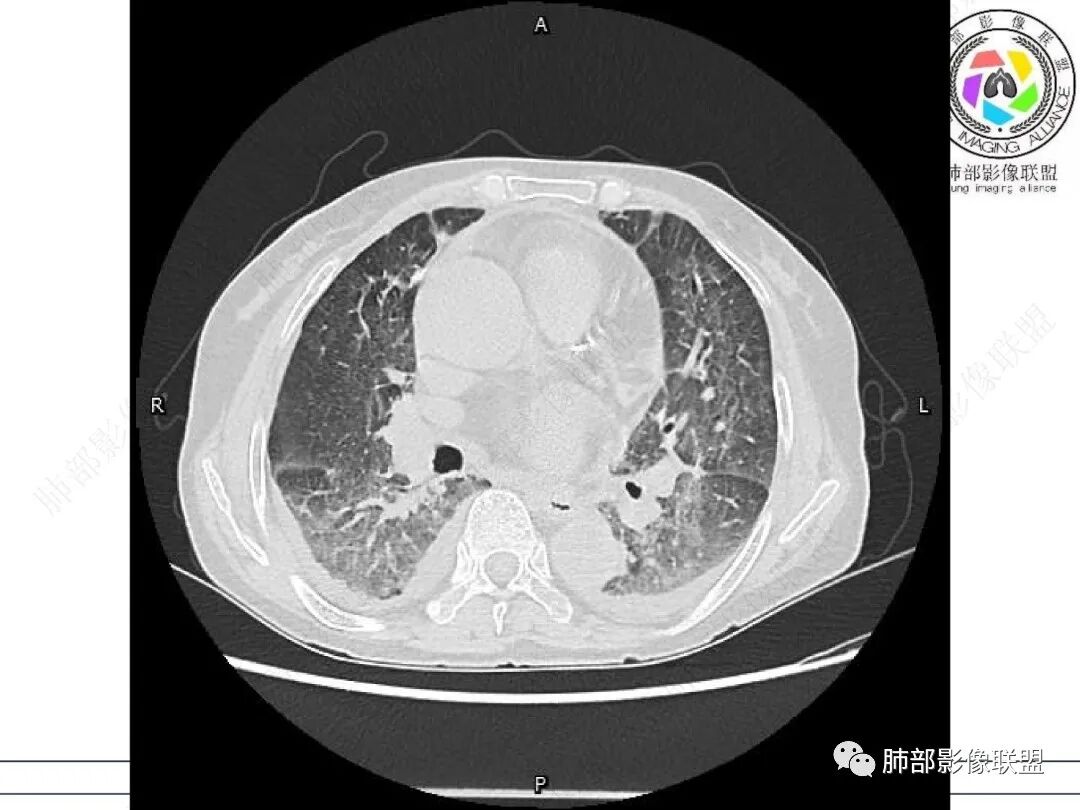

心脏大,胸腔积液,小叶间隔增厚,双肺磨玻璃影,考虑存在肺水肿,另双肺间质性炎性,类风关病史,考虑CTD-ILD,左肺上叶结核可能。

两肺叶后肋膈角区见多发蜂窝状结构破坏表现,双肺叶小叶间隔增厚,左肺上叶后段及舌段和右肺中叶胸膜炎性肉芽肿特点,双侧胸腔少量积液,有类风湿性关节炎治疗史,结缔组织相关性间质性肺病。

发热,有类风湿性关节炎、糖尿病基础病,长期口服激素及免疫抑制剂,双肺多发磨玻璃影及小叶间隔增厚,蜂窝影,支气管扩张考虑非特异性间质性肺炎存在,左肺上叶不规则结节影,周围长毛刺局部肺气肿,考虑慢性炎症,结合pct及crp升高考虑细菌感染,另真菌g升高考虑结合宿主因素,真菌感染需要积极排除。

老年,外阴溃疡加发热,感染指标明显有异常,血气分析,过度呼吸及低氧血症,宿主因素,糖尿病和激素,基础疾病RA。影像,双下肺体积有缩小,有蜂窝?双肺磨玻璃,多发结节,双侧胸水。树芽不明确。是否有旧片,这个患者有UIP背景,是否感染或者UIP急性加重,或者基础上合并肺栓塞及肺水肿?长期激素,没有提供CD4细胞亚群,存在2种情况,1,风湿病没有压制住,肺考虑CTD相关性间质改变,压制过猛,结合感染指标,奴卡是有可能的。激素加糖尿病,结核也带排,激素加磨玻璃加G实验阳性,PCP也带排,临床信息太少,进一步排查

老年女性,有高血压糖尿病及类风湿性关节炎病史,发病前发烧。影像学两肺弥漫性磨玻璃影及斑片影,有渗出性病变亦有间质性改变,支气管血管束增粗,有牵拉扭曲有小气管扩张及间质增厚,两肺下叶胸膜下少许蜂蜜状影。两侧胸腔积液。考虑类风湿性关节炎肺内浸润?合并真菌感染?

老年女性,类风湿关节炎病史多年。发热。以两肺下叶为主弥漫磨玻璃及网格状透亮影,透亮度减低,局部小蜂窝状改变;两肺胸膜下散在几枚实性病灶;双侧胸腔积液。考虑RA-ILDNSIP

两下肺多发蜂窝状表现,双肺小叶间隔增厚,双肺磨玻璃影及部分炎性肉芽肿表现,双侧胸腔积液,有类风湿性关节炎治疗史,结缔组织相关性间质性肺病。患者C反应蛋白和降钙素原都高,是否合并细菌感染

女,71,外阴疼痛2周,发热1周。类风关、高血压、高血糖、卵巢囊肿、肠粘连、胆囊结石等病史及相关药物治疗史。胸部CT:两肺弥漫磨玻璃,血管束增粗,两下肺后肋膈角多发蜂窝,对称分布,双侧胸腔少量积液,纵隔窗心脏大血管影明显增宽。考虑混合性病变,CTD-ILD,并肺水肿?并PJP?。

双肺下叶多发蜂窝影,双肺小叶间隔增厚,双肺磨玻璃影,双侧胸腔积液,有类风湿性关节炎,考虑结缔组织相关性间质性肺病,合并感染

①影像表现复杂:较弥漫间质性改变,对称磨玻璃密度为主,小叶间隔增厚,有一定重力分布趋势,未见明显纤维化,气囊及蜂窝位于肺边缘,未见典型“月弓征”。心脏影增大,双侧胸腔积液。

这即可见于间质性肺病,也可见于真菌感染(如PJP)、病毒感染,类风湿,以及肺水肿等等。

一般而言,如存在磨玻璃密度影浑浊,有重力分布趋势,肺表面蜂窝影,胸腔积液等等,并不常见于单纯PJP,除非其他因素叠加。

患者存在肺水肿应当是合理的解释。其他旁证还有,心脏影增大,肾小球滤过率降低,双侧胸腔积液等等……